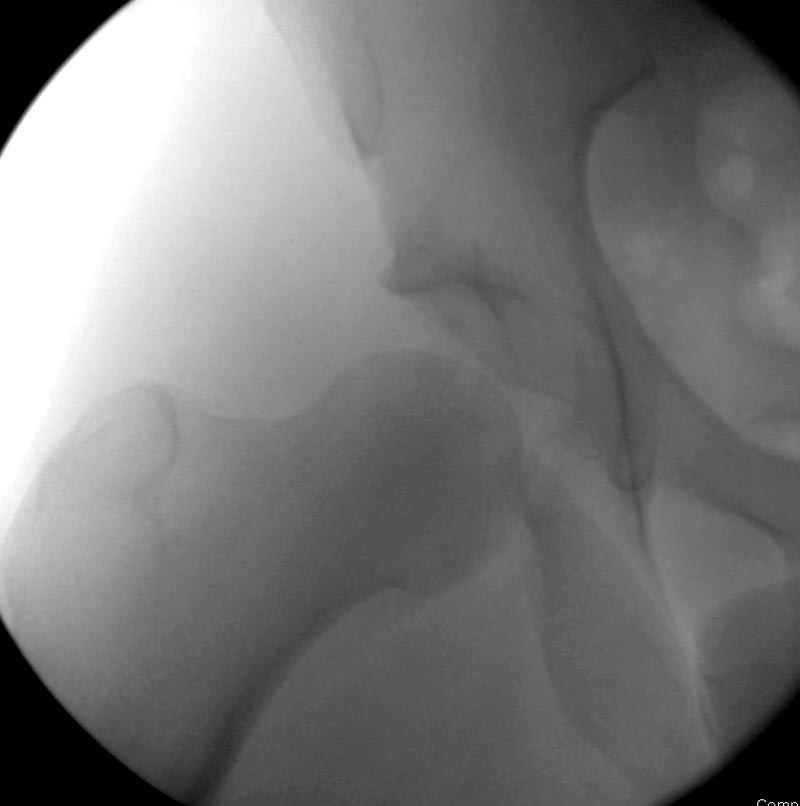

5:24 Рентгенограмма таза, вызывают врача ортопеда (снимок N1), его диагноз: закрытый переломо-вывих правого тазабедренного сустава, получает добро на закрытую репозицию в приемном отделении

5:38 Дважды неудачная попытка закрытой репозиции в приемном отделении

N 2

6:20 ответстенный врач принимает решение о репозиции в условиях операционной, предупреждаются родственники и больной, что при неудачной закрытой репозиции, о возможности открытой репозиции и фиксации задней стенки вертлужной впадины.

7:30 начало операции, больной на спине, попытка репозиции после анестезии N3, укладка больного на боку, доступ Kocher- Langenbeck, состояние седалищнего нерва около 2.5см кровоподтек, через joistick головка бедра приподнята, освобовождение сустава, фрагмент заднего края более 3х4 см репонирован на свое место. После промывания

сустава, репозиция вывиха (N4), фиксация фрагмента 2.7(4) мм шурупами и допольнительно реконструктивной пластиной на 8 дырок, фиксация 3.5мм шурупами проксимально и дистально.

Интраоперционные N5 косая запирательная и N6 подвздошный снимок